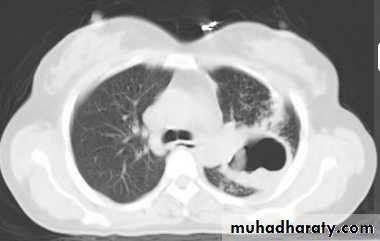

NECT with lt. pulm. A. thrombosis2- Showing shape of intrapulmonary or pleural opacity, detecting calc. or cavitation when plain CXR not conclusive.

7- pulm. embolism.

Only structures seen normally in CT scan of chest are blood vs., fissures and walls of bronchi(as on CXR).